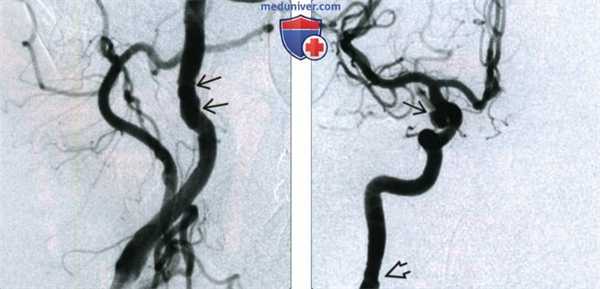

(Слева) Цифровая субтракционная ангиография правой общей сонной артерии, косая проекция. Выпячивания шейного сегмента внутренней сонной артерии, характерные для фиброзно-мышечной дисплазии.

(Справа) Цифровая субтракционная ангиография в передне-задней проекции, тот же пациент. 6-мм аневризма задней соединительной артерии, разрыв которой привел к субарахноидальному кровоизлиянию. В шейном сегменте внутренней сонной артерии видны изменения, характерные для фиброзно-мышечной дисплазии.

4. Ангиография:

• Цифровая субтракционная ангиография (DSA): золотой стандарт диагностики, 3 варианта:

о Тип 1 (85%): признак «четок», медиальная фиброплазия

о Тип 2 (10%): протяженный участок стеноза, фиброплазия интимы

о Тип 3 (5%): асимметричное выбухание с одной стороны артерии; периадвентициальная фиброплазия